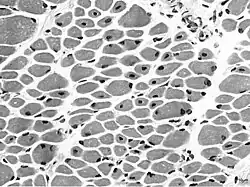

Miopatia (do grego μυοπάθεια, myo=músculo, pátheia=padecença, doença) é designação genérica das afecções e doenças musculares em que as fibras musculares não funcionam em muitas vezes, o que resulta em fraqueza muscular. Cãibras musculares, rigidez, espasmo, tetania e o "manobrismo do levantar" são sintomas e sinais associados à miopatia.